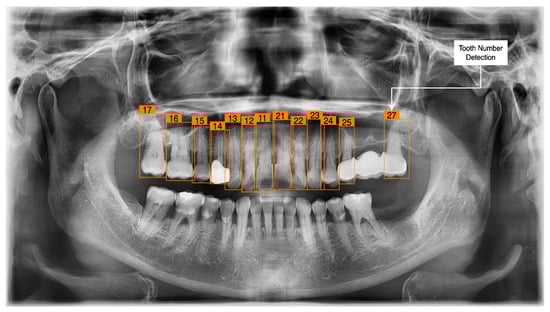

3.3. Tooth Identification through YOLOv5

3.4. Determination of Tooth Stage through U-Net and YOLOv5 Integration